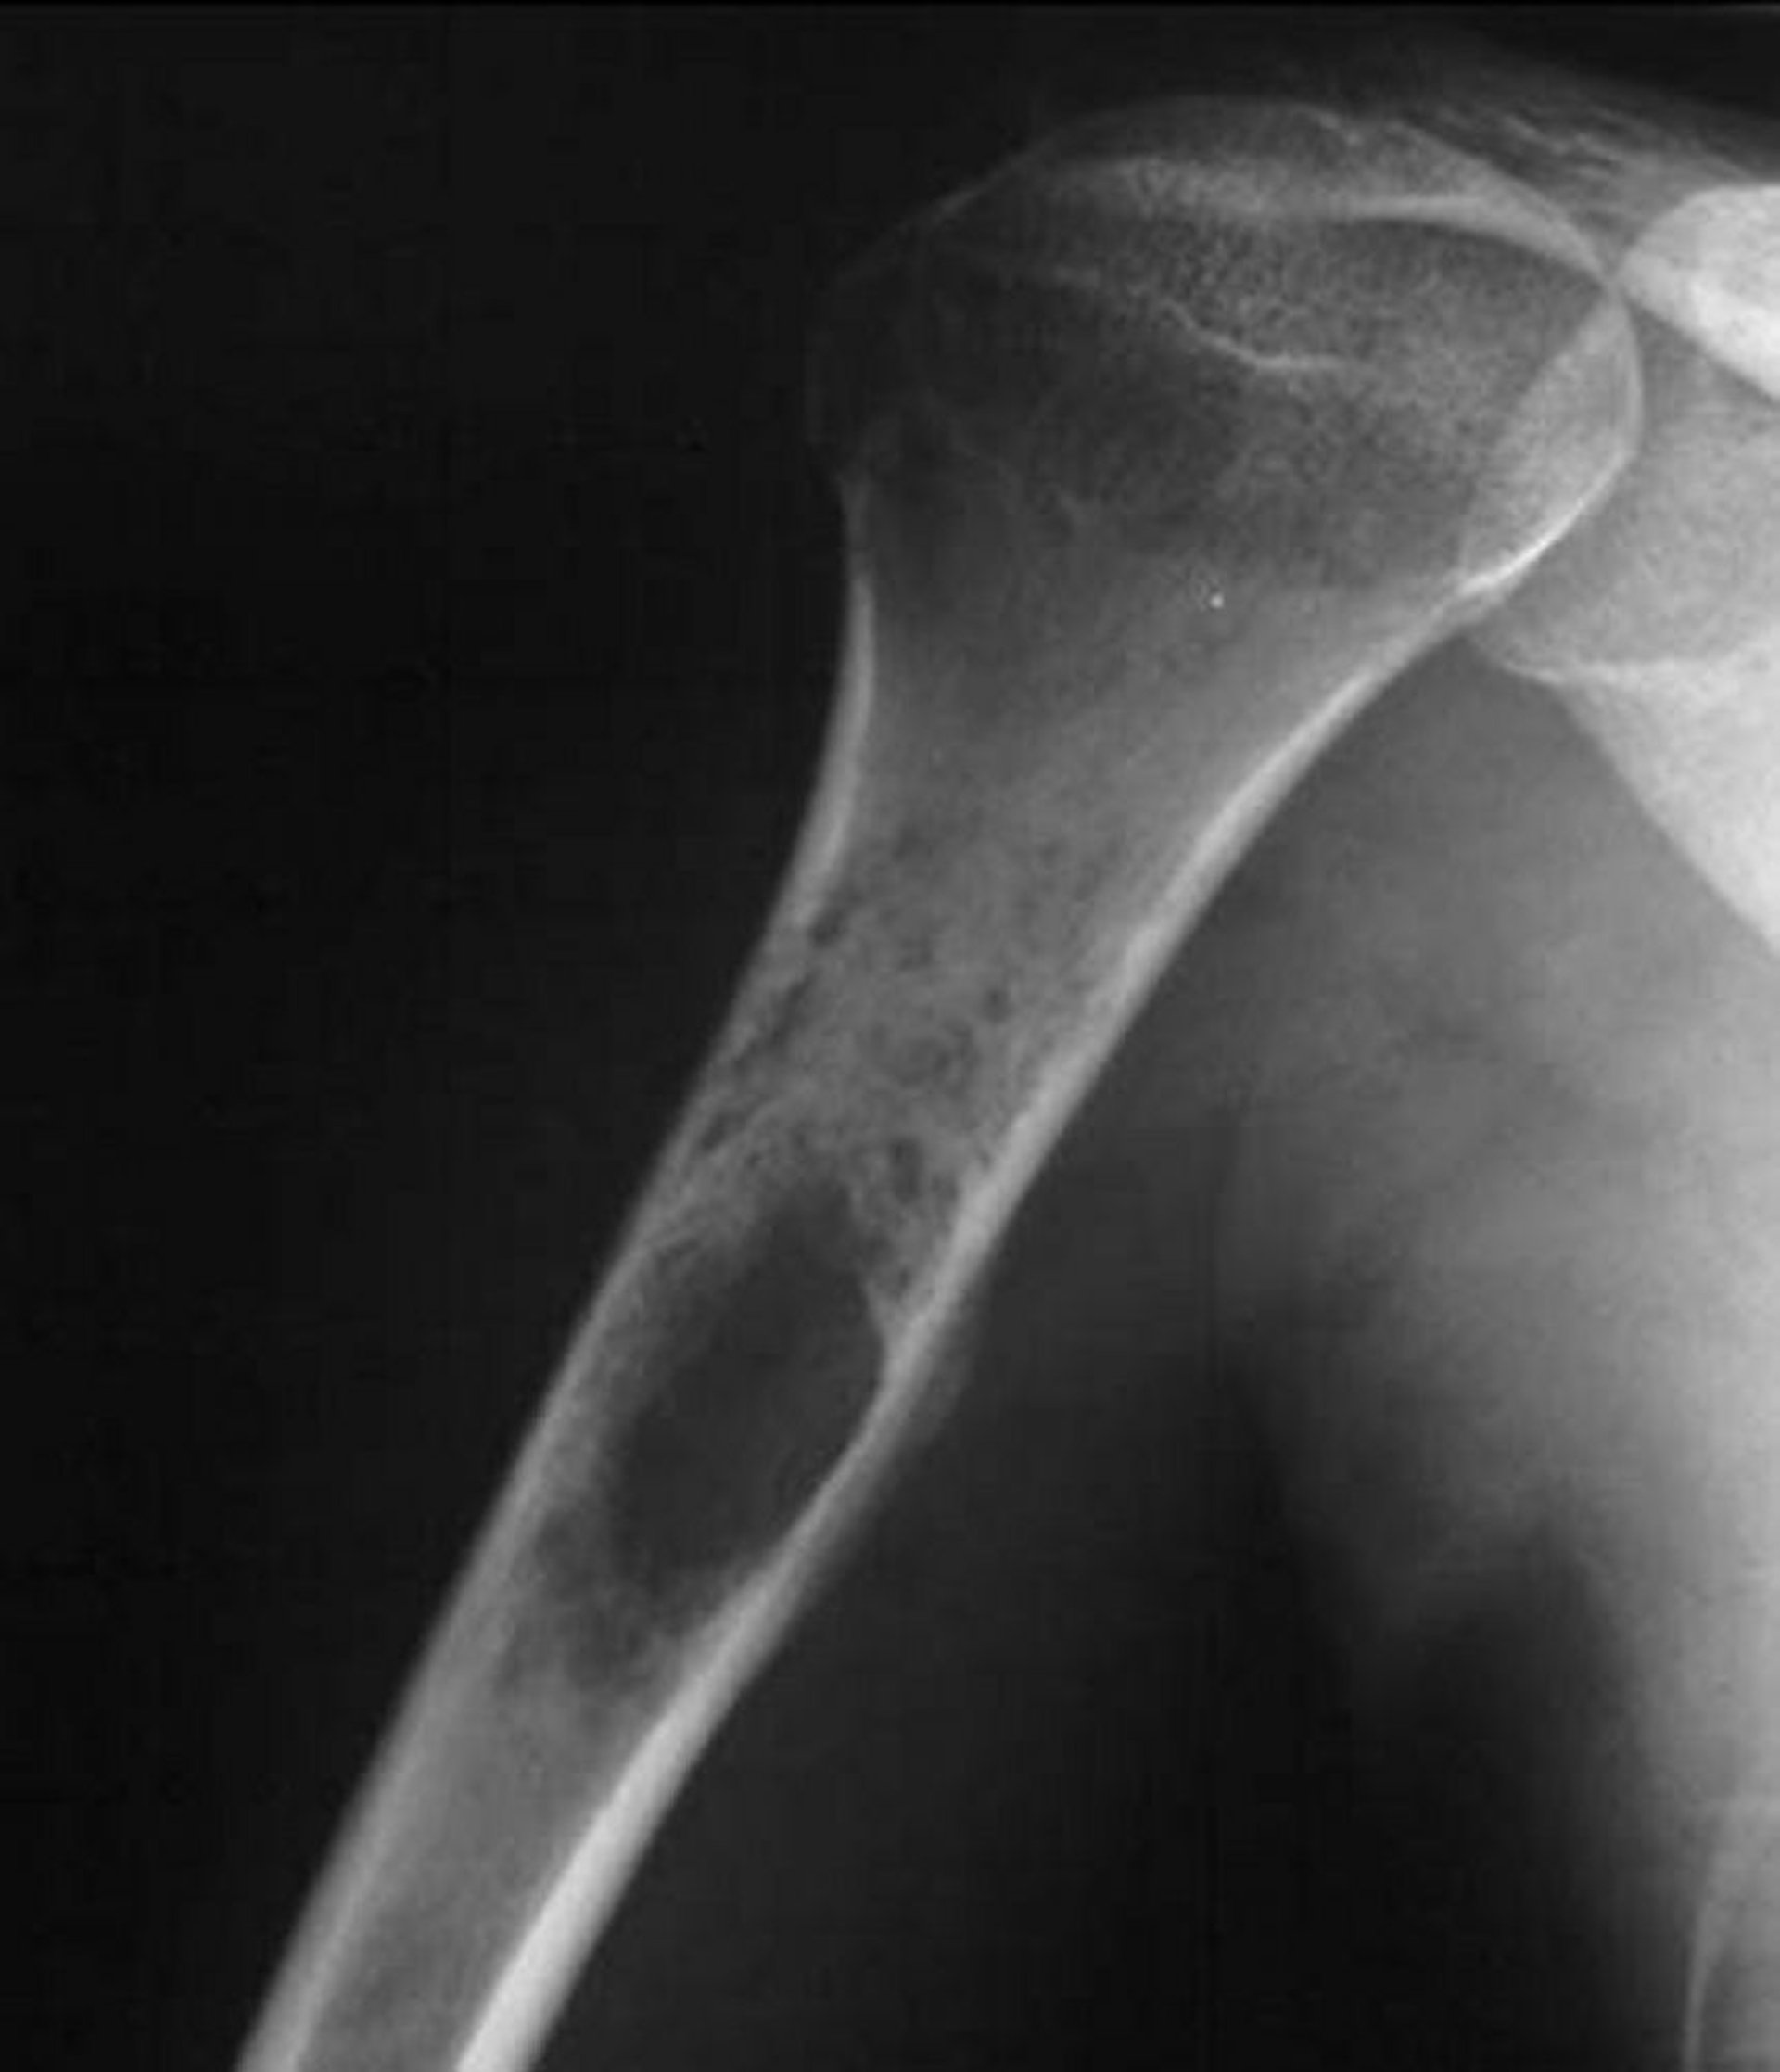

Questa radiografia della spalla mostra un tumore distruttivo permeativo che nasce nell'omero prossimale, che è tipico del sarcoma di Ewing.